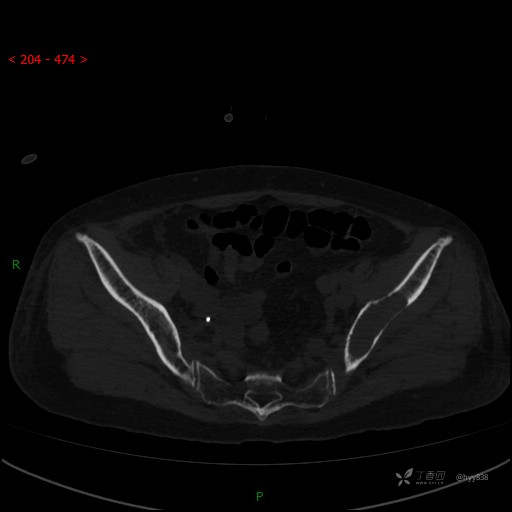

CT平扫

骨窗